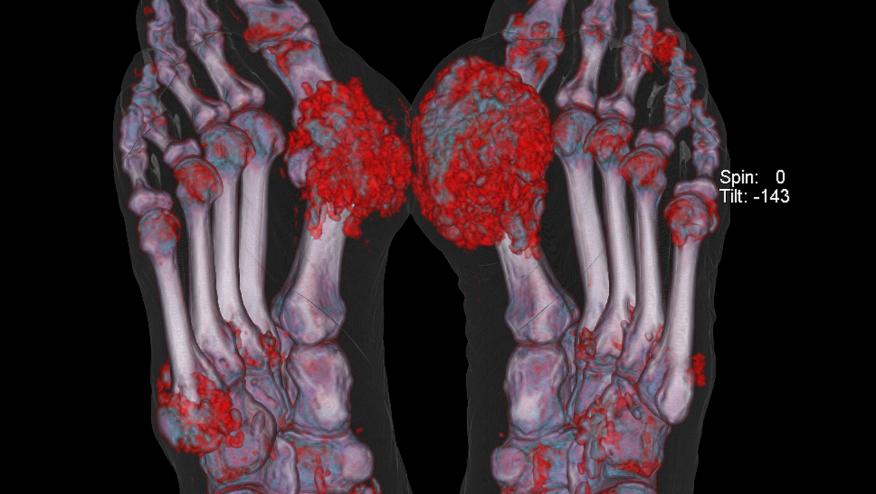

Dalbeth and coworkers studied 92 patients with gout and using DECT scanning have shown those with urate deposition on DECT were 8.5-fold more likely to have erosive disease on plain radiographs. Of the 920 joints assessed by DECT, 16.6% of them had dual-energy CT (DECT) urate deposition. These results suggest urate crystal deposition is integral in developing structural joint damage in gout.